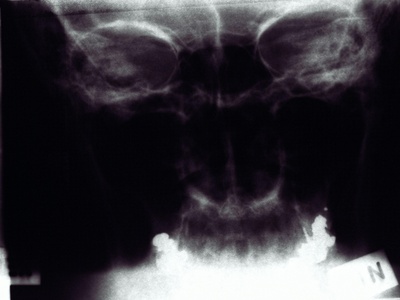

Hip

The hip is a deep ball-and-socket between the femoral head and acetabulum at the hip; it permits weight-bearing multi-axial motion with about 120° flexion and stable rotation. Clinically notable for osteoarthritis and frequent total hip replacements.